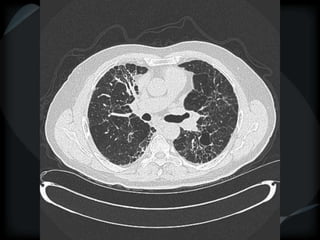

PHTN – PA 39mm

39.2mm

PHTN and septal thickening

? PVOD